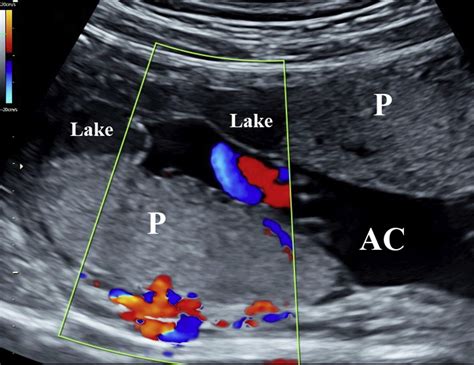

The placenta is a temporary organ that develops in the uterus during pregnancy. It serves as a lifeline between the mother and the fetus, facilitating the exchange of nutrients, gases, and waste products. Lakes In The Placenta refer to small, fluid-filled spaces within the placental tissue. These lakes are not typically visible to the naked eye but can be detected through advanced imaging techniques and histological examinations.

• Ultrasound Imaging: High-resolution ultrasound can sometimes detect the presence of lakes, although this method is not always reliable.